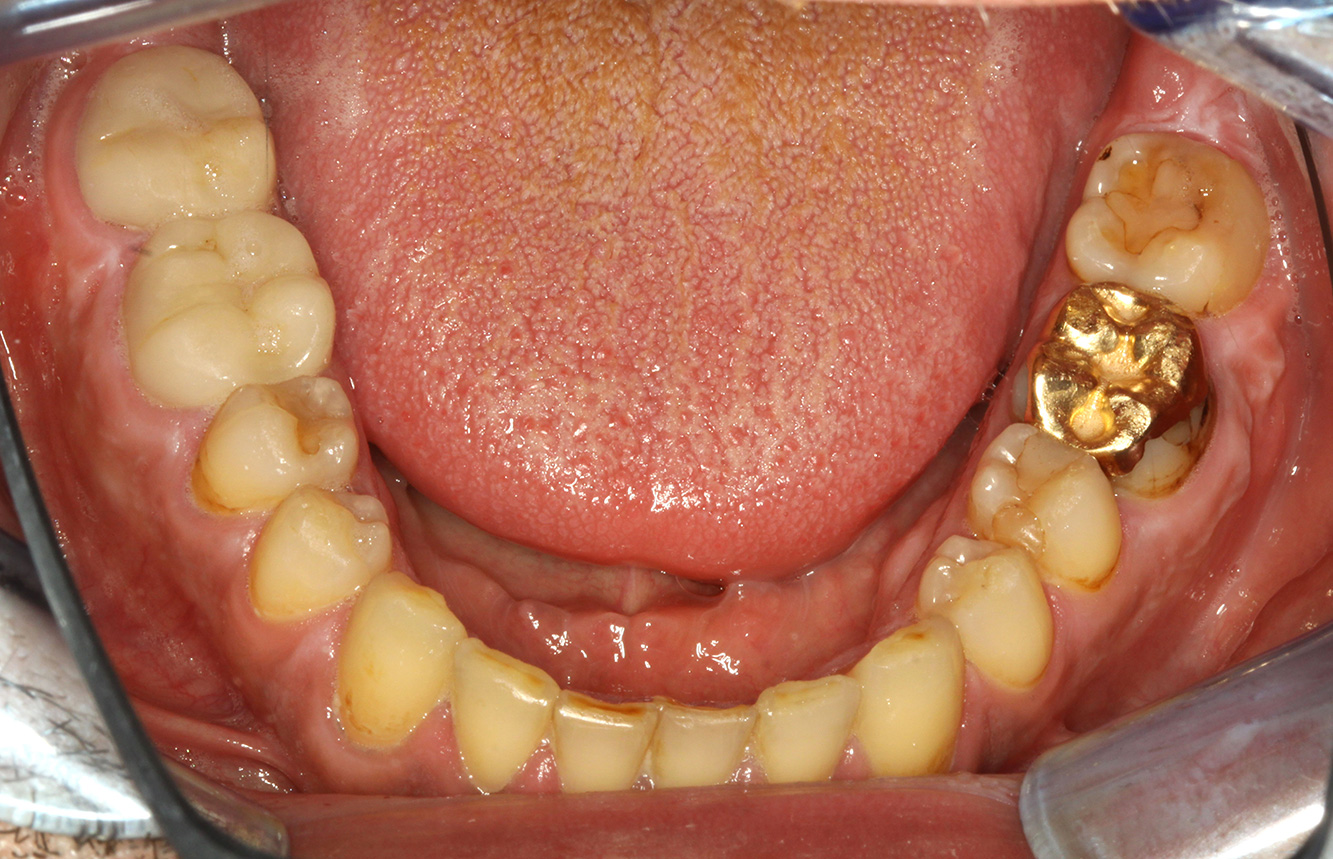

In the medical history, the 55-year-old patient states that he has no systemic disease and is not taking any medication. The patient’s lifestyle is similarly unremarkable. The patient has a few tooth restorations and two implants (2nd and 4th quadrants). On the basis of current findings, gingivitis is identified in an otherwise stable periodontal condition on the reduced periodontium (stage III, grade A). more

The healthy patient with pre-existing periodontal disease & peri-implantitis

Paciente sana con enfermedad periodontal previa